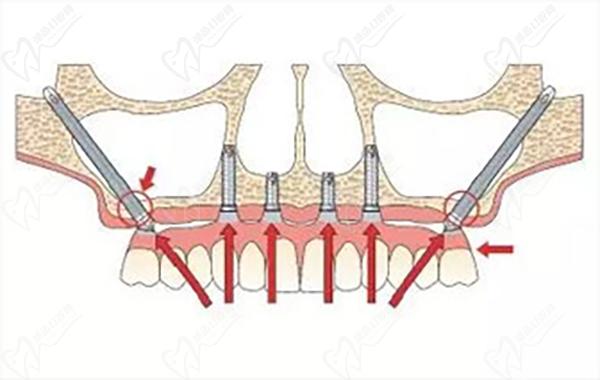

穿顴種植手術(shù),是通過將兩顆超長(zhǎng)植體斜植入顴骨來獲得超高的固位成效,然后在前牙區(qū)在垂直植入2-3顆普通植體,對(duì)于頜骨吸收情況比較重的牙友可以使用四顆穿顴種植體。穩(wěn)定性非常強(qiáng),是即刻種植修復(fù)技術(shù),大大縮短了種植牙時(shí)間,避免了大量植骨帶來的愈合等待期和風(fēng)險(xiǎn)。

穿顴種植牙示意圖:

穿顴種植牙示意圖